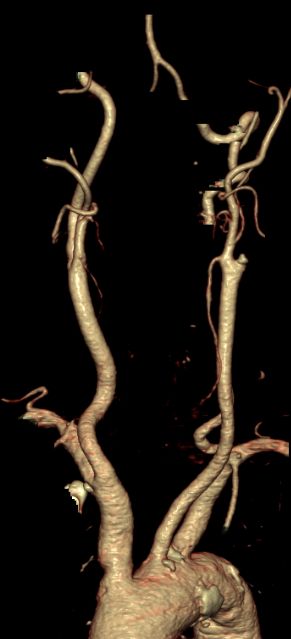

ACI-Verschluß 63-jährige Frau, die wegen TIA eingeliefert wurde. Daraus entwickelte sich eine komplette Halbseitensymptomatik. Das CT zeigt einen Abgangsverschluss der linke ACI.

CT-Angio

Gut markierter Media-Infarkt